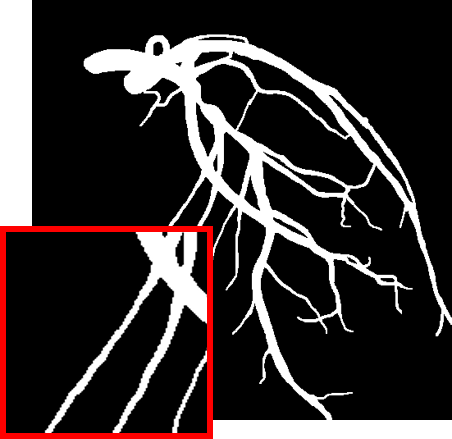

4.1 XACV Dataset

We collect 111 complete records of coronary artery X-ray videos from 59 patients, encompassing the injection, flow through the blood vessels around the heart, and dissipation of the contrast agent. Subsequently, we establish the XACV (X-ray Angiography Coronary Video) dataset. Each video consists of an average of 86 frames of high-resolution coronary artery X-ray images, with an equal distribution of left and right coronary arteries. We invite experienced radiologists to annotate the vascular regions, focusing on one or two frames where the contrast agent is most prominent in each video. These annotations are used only for evaluation in our method, not for training, maintaining the unsupervised nature of our approach. The data collection protocol involves several key steps, including patient preparation with informed consent and metal object removal, image capture using a Philips Allura Xper FD20 machine for standardized frontal (PA) and lateral views, DICOM file storage, and de-identification for patient privacy. Experienced radiologists perform diagnostic annotations using standardized tools and methods, with multiple annotations to enhance accuracy. Quality control measures, secure data management, and strict adherence to ethical guidelines and privacy regulations are implemented throughout the process. The XCAD dataset contains only a single image, and the CADICA video dataset does not provide corresponding ground truth. Therefore, in the following experiments, we conduct all the analyses on our collected XACV dataset and the corresponding GT for each sequence. In Figure 5, we show that compared to other publicly available datasets, XCAD (Ma et al., 2021) and CADICA (Jiménez-Partinen et al., 2024), our dataset exhibits finer annotations in the vascular regions, providing an advantage for future related tasks. The development and use of our dataset have been approved by our institution’s IRB. We will make the XACV dataset publicly available.

We calculate the AUROC and AUPRC in Figure 6. We normalize the model’s final layer output to [0, 1] to use it as the probability for calculating AUROC and AUPRC. Our model performs favorably against other methods on both AUROC and AUPRC. We also provide visual comparison results in Figure 7, demonstrating our vessel segmentation results are more accurate, complete, and closer to the ground truth masks. Moreover, in some sequences, our method even performs on par with supervised U-Net (Ronneberger et al., 2015), as U-Net might face an overfitting problem with insufficient training data. Additionally, we provide visual comparisons on the CADICA (Jiménez-Partinen et al., 2024) dataset, which is also a coronary artery X-ray video dataset but without ground truth labeling. Figure 8 demonstrates that our test-time training scheme generalizes better than existing methods. Due to the space limit, we provide more visual comparisons in the appendix.